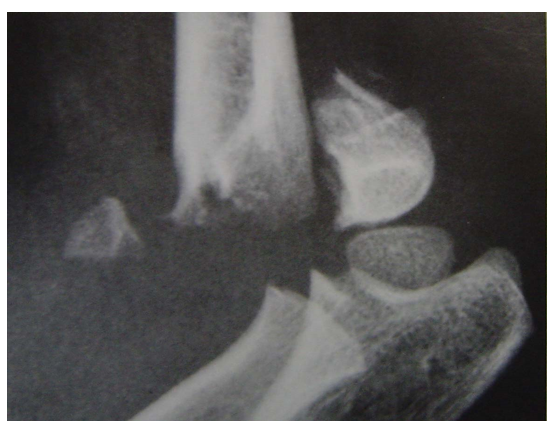

Baumann角

A 肱骨干中线a

B 作a的垂线b

C 通过外髁骺线

∠A,原始Baumann角

∠B ,现在Baumann角

正常72度[64~81],81度以内,不会发生肘关节内翻